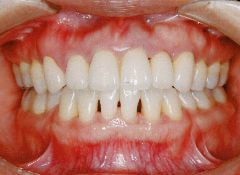

治療例1 (インプラント補綴+矯正)